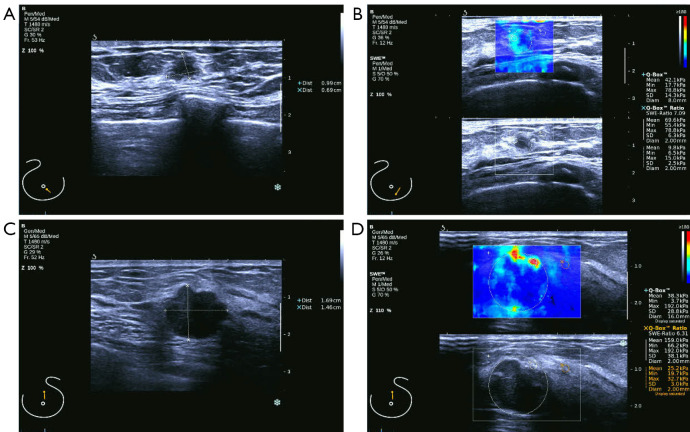

Methods: A total of 67 patients who underwent breast cancer surgery between January 2017 and January 2021 were recruited for this retrospective study. Among 70 breast cancer lesions in the included patients, 31 lesions were HER-2 negative, and 39 lesions were HER-2 positive. SWE imaging was conducted and Young's modulus values including mean elastic modulus (Emean), maximum elastic modulus (Emax), and minimum elastic modulus (Emin) were measured. Receiver operating characteristic (ROC) curve analysis was used to evaluate the diagnostic efficacy of the imaging parameters for HER-2 positivity.

Results: The HER-2 positive group had a higher proportion of lesions with a diameter of ≥20 mm. The Emax value was significantly lower in the HER-2 positive group compared to the negative group (P<0.05). The highest area under the curve (AUC) value (0.800) was observed for the combination of Emax, lesion size, and calcification, with a sensitivity of 66.7% and specificity of 83.9%.

Conclusions: Emax combined with lesion size and calcification showed a moderate association with HER-2 positivity, suggesting a potential role for SWE in complementing established diagnostic methods. These findings suggest that SWE parameters, in particular Emax may be useful in the non-invasive assessment of HER-2 status in breast cancer.